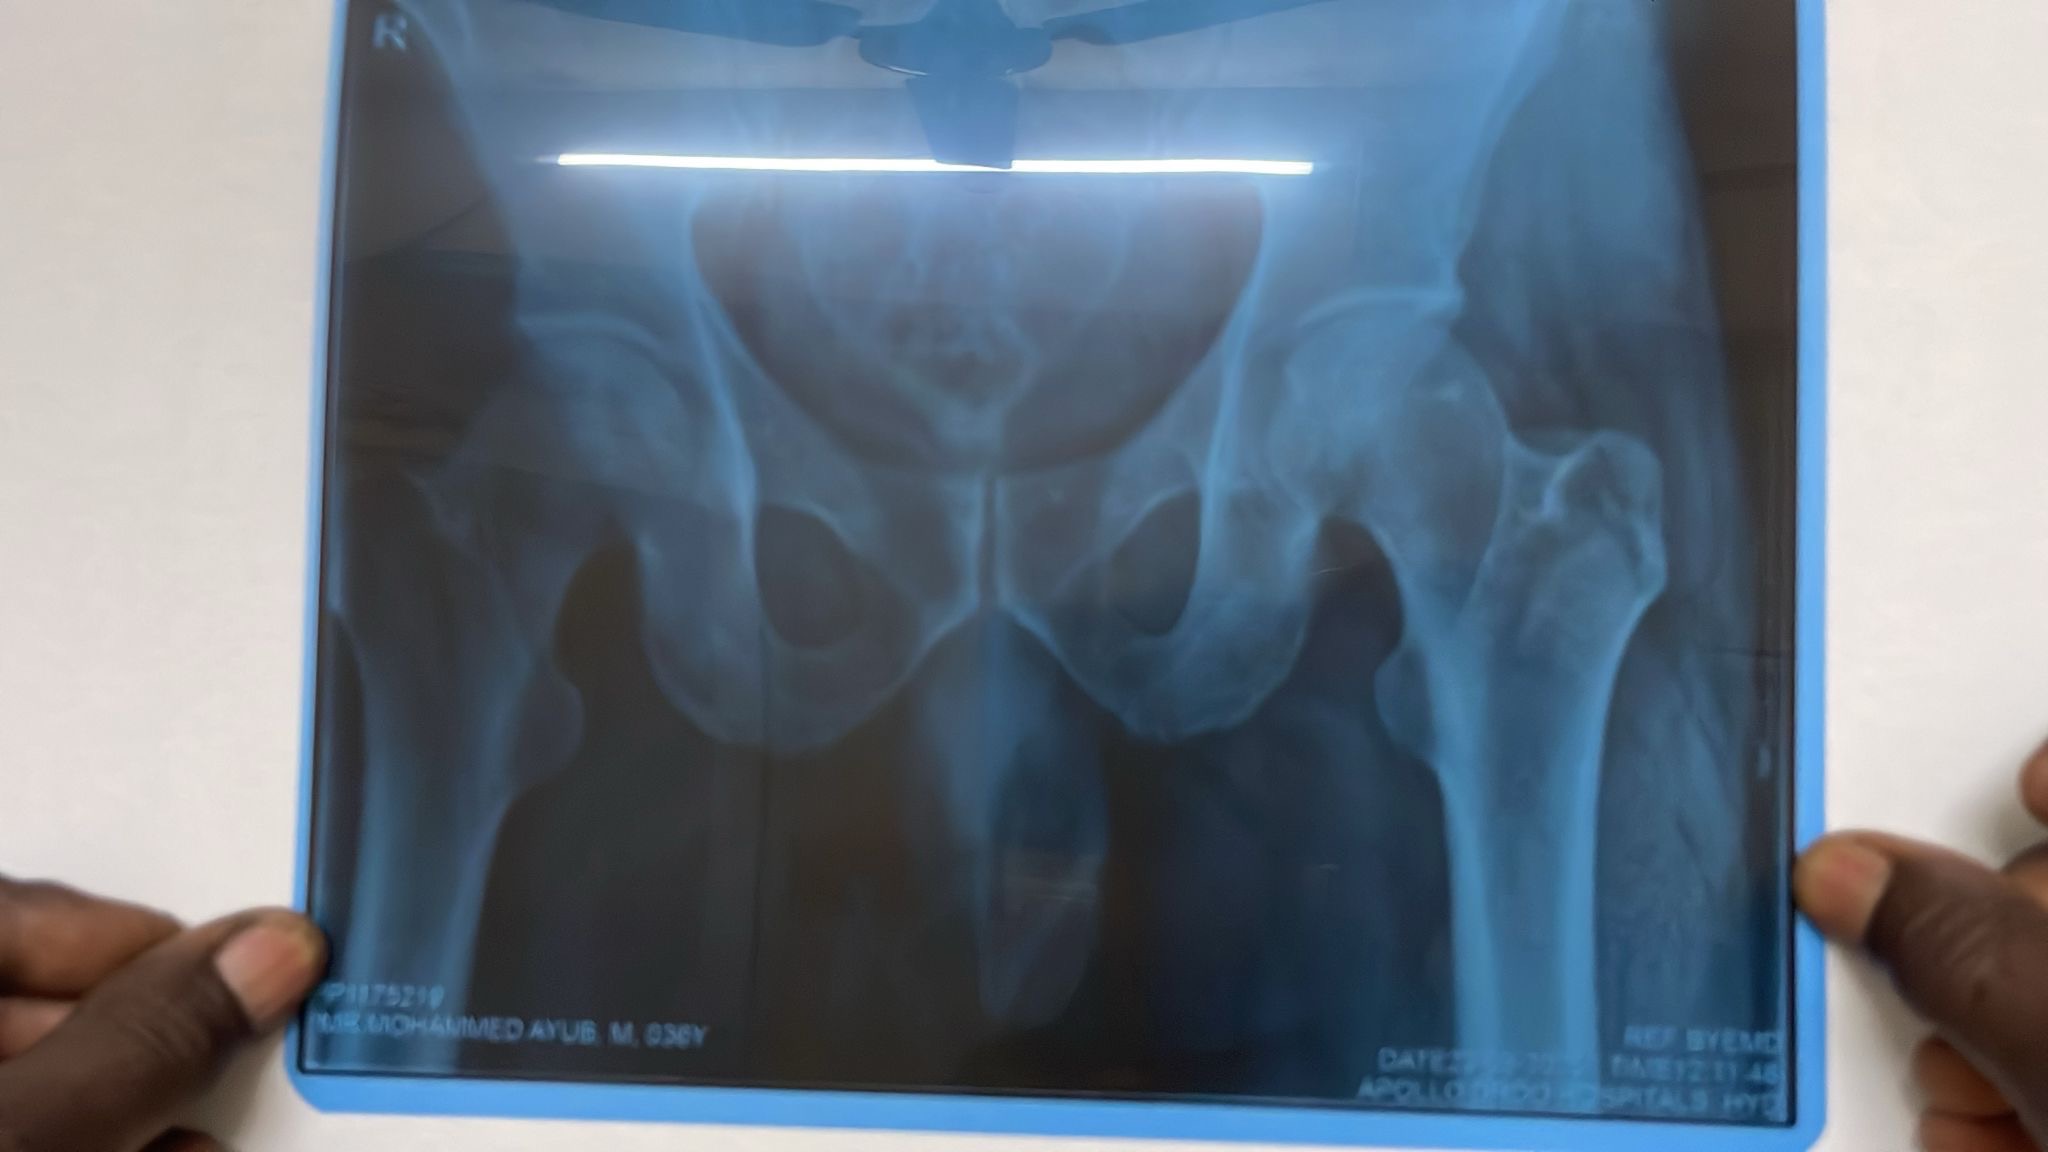

I am reaching out with an urgent request to support a poor family in desperate need. Mohammed Ayub, the sole breadwinner for his family of 7—including 3 very young children—was recently involved in a tragic accident. He has sustained life-threatening injuries and is in critical condition.

He urgently requires multiple surgeries, including on his spine, ribs, cervical area, hand, and jaw. His ribs have punctured his lungs, and immediate treatment is the only chance to save his life.